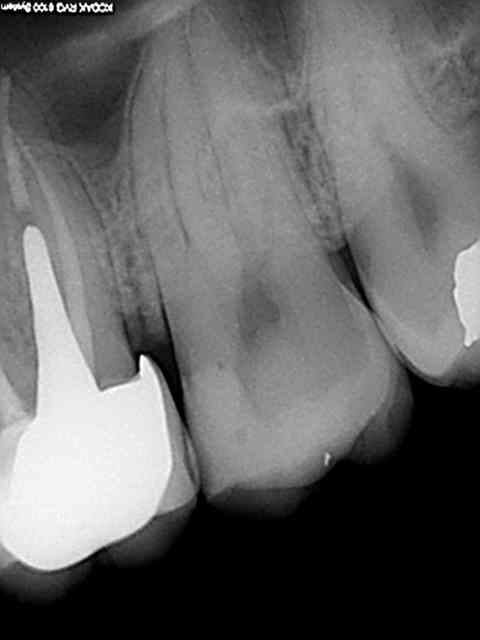

Sinon une fois en place la métafix est une tuerie, gaffe à ne pas faire le mur trop épais car si l'espace est trop étroit entre le mur et la paroi proximale de la cavité le compo a du mal à fuser ( voir la 37) lors de son foulage (a moins d'utiliser du sdr fluide par exemple.

R34 g7agre - Eugenol

R36 mldzgm - Eugenol